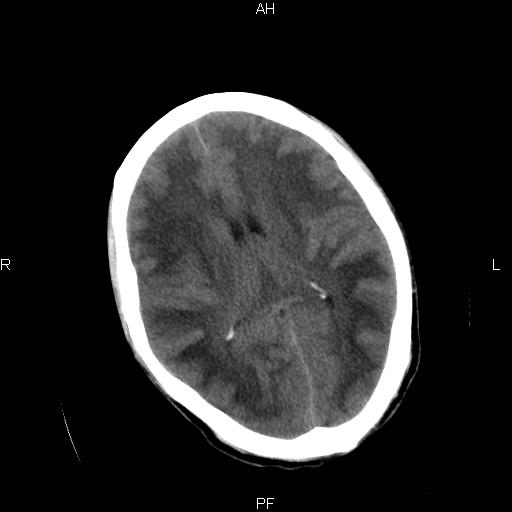

男性,45岁,缄默少语,四肢无力一个月。骨窗未见明确异常。

弥漫性脑白质低密度症

对称性脑白质广泛低密度。有高血压史及大量饮酒史吗?

考虑重度脑白质稀疏症。

弥漫性脱髓鞘病变,建议mri检查。

双侧弥漫性对称性全累及性(外囊亦有累及)脑白质病

患者病程月余,脑沟裂闭合,第三脑室较窄,提示应该有较明显的脑白质水肿,考虑有持续性炎性病变

综合考虑脑白质感染性或非感染性炎症可能性大,不排除为克雅氏病